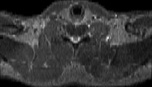

Visible Human male: Sectio transversalis 1279

CT

NMR

Pd T1 T2